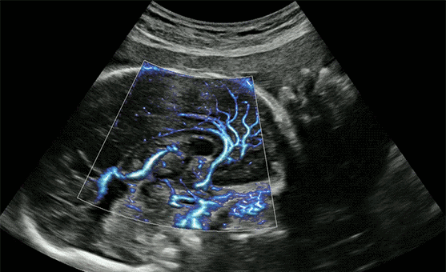

CrystalLive?是三星最新的超聲成像引擎,同時增強了2D圖像處理能力、3D渲染能力和彩色信號處理能力,能夠在復(fù)雜情況下提供出色的圖像性能,具備檢測外周血管、微循環(huán)血流的能力。

2D成像方面,Hera i10集成了包括ShadowHDR?、HQ-Vision?、ClearVision等多項具有三星“血統(tǒng)”的技術(shù),加強了圖像的陰影抑制、減少偽影、緩和模糊區(qū)。